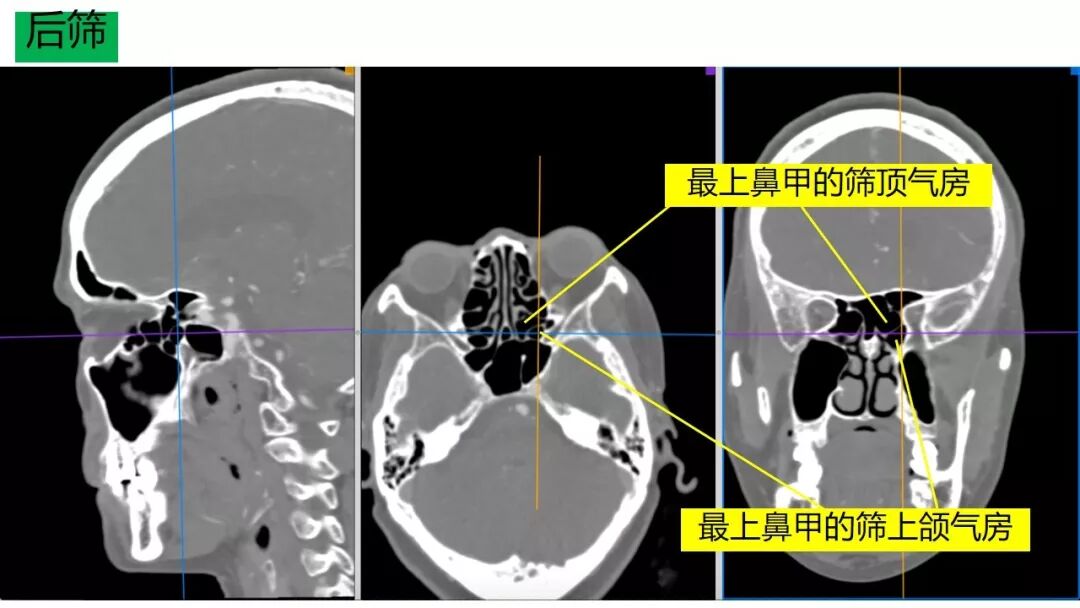

内镜修补